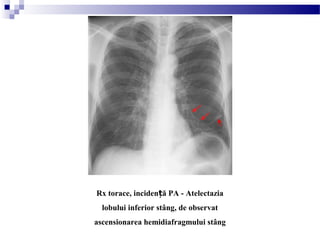

Rx torace, inciden ă PA - Atelectaziaț

lobului inferior stâng, de observat

ascensionarea hemidiafragmului stâng